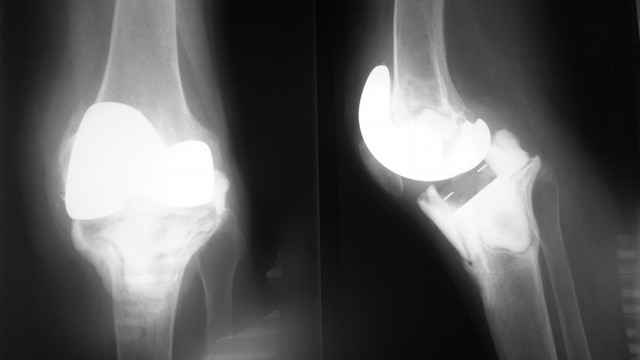

Уважаемые коллеги, случай обсуждавшийся на форуме около года назад имеет грустное

продолжение.Пациентка вернулась в отделение через 1.5 месяца после операции, с

нагноением.Протез удалили, установили цементный спейсер, с использованием компонентов

удаленного протеза.Воспалительные явления на сегодняшний день купированы.Что

дальше?Думали о репротезировании с использованием интрамедуллярного

стержня,"связанного" протеза в арсенале нет. Но в последнее время все чаще приходят мысли об

артродезе...возникает вопрос о величине укорочения(по предварительным оценкам около 10

см).Какой вариант выбрать?На что еще стоит обратить внимание?